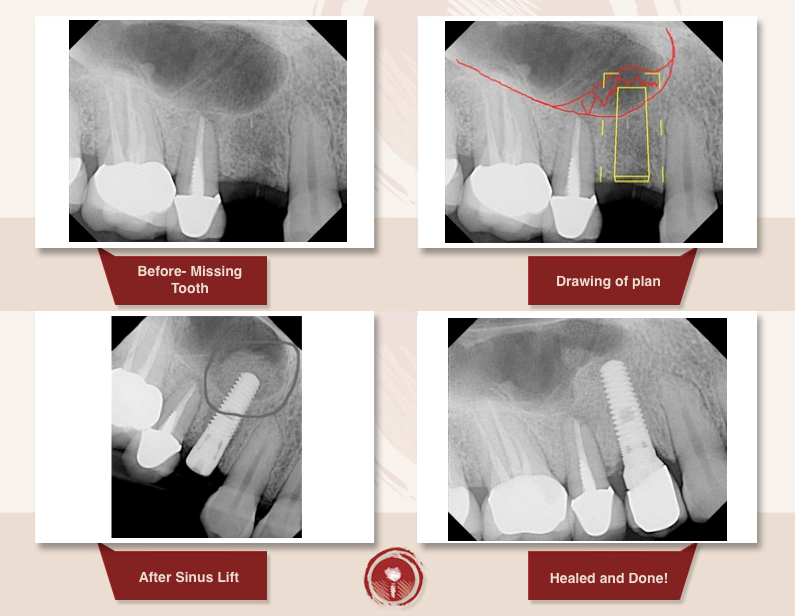

Синус ліфтинг

Операція синус ліфтинг

Це хірургічна операція по нарощуванню кісткової тканини в бічних відділах верхньої щелепи, для якісного встановлення імплантатів.

При більшій пневматизації показаний закритий синус ліфтинг або м’який (soft) з доступом через канал ложа імплантату.

При наявному обсязі кісткової тканини менше 5 мм показаний відкритий синус ліфтинг – пластика дна верхньощелепної пазухи з доступом-перфорацією передньої стінки пазухи.

Закритий синус ліфтинг характеризується як менш травматично хірургічне втручання.

Суть цієї операції полягає в формуванні доступу через гребінь альвеолярного відростка в місці передбачуваного встановлення імплантату.

Для маніпуляцій при відкритому синус лифтингу доступ здійснюється через передню стінку гайморової пазухи.

Операція відкритого синус ліфтингу включає кілька етапів.

Після ушивання м’яких тканин, щоб уникнути відторгнення імплантату необхідний час для повної інтеграції, ремодуляції і осифікації (окостеніння) остеотропного матеріалу.

Традиційно вважається, що повний цикл репаративного остеогенеза (регенерація кісткової тканини) становить півроку, але виробники остеоіндуктівних матеріалів повідомляють про формування необхідної механічної міцності тканин через 4 місяці.

Таким чином, на цьому терміні доречно проведення рентгенологічного обстеження з метою визначення обсягу сформованих тканин, їх рентгенологічної контрастності і щільності, тобто ступенем мінералізації і придатності до установки імплантатів.